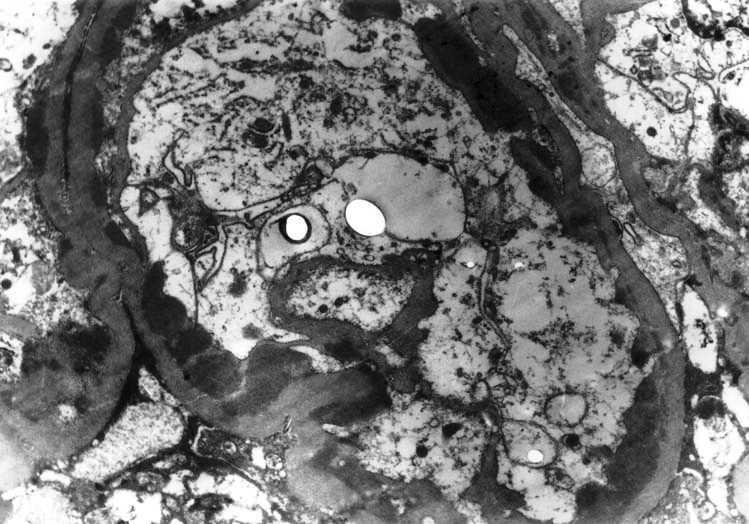

Figure 1. Portions of two capillary loops showing extensive fusion of foot processes in a case of minimal change disease.

MCD was the second most frequent lesion underlying NS in children in this study. It used to be the leading cause of INS in children, but many researchers have found a declining prevalence of this lesion throughout the world in recent years.9 The EM study was essential for the diagnosis of this disease, in that it demonstrated the most important morphological lesion of the disease, i.e., the fusion of foot processes. Although, the diagnosis of MCD can be suspected on LM and IF examinations, it is only the EM study that conclusively establishes its diagnosis, as shown in Figure 1. We acknowledge the fact the potential role of EM in establishing a diagnosis of MCD in a pediatric population is not without controversy, especially, in the perspective of developing countries. The definitions of essential and helpful roles of EM have been derived from studies done in developed countries, and may not be equally relevant for resource constrained developing countries. It could be argued that children presenting with nephrotic-range proteinuria and a normal appearing renal biopsy on LM could be presumed to have MCD. By this argument, EM would not be essential in establishing a diagnosis of MCD. Nevertheless, standard of care in Western countries would dictate that EM is deemed essential.